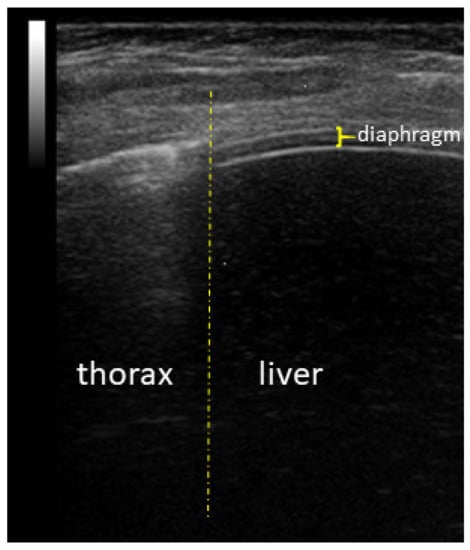

Diaphragm Ultrasound